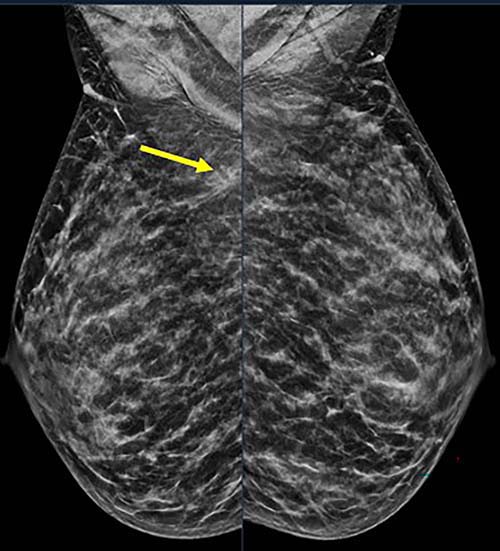

40-year-old patient presents for routine screening. Family history of paternal grandmother age 55. Extremely dense breast tissue is noted on mammography right and left mediolateral oblique (side angle) view. In addition, an area of architectural distortion is seen at the posterior right breast on right view (see arrow).